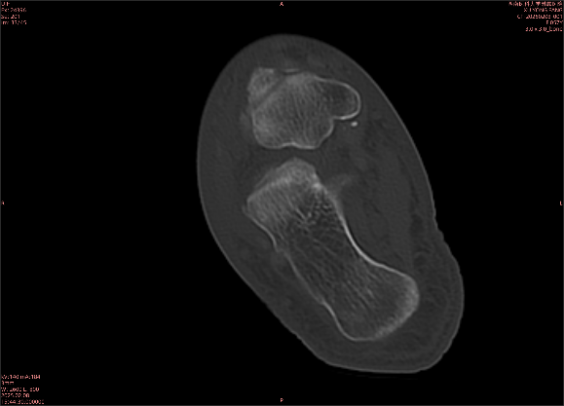

举例图像

图2

专业解释看不懂没关系,大家看图1和图2就可以了,这是同一个患者跟骨的磁共振和CT图像,图1的红色箭头指示的黑线就是磁共振图像显示的骨折线,一目了然。而对比图2的CT图像上并未显示异常。